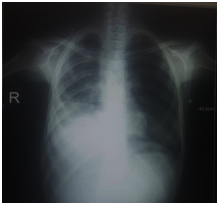

During follow up a mild fistula and pleural dead space happened, but PT clinically got better. After 5 months the fistula continued and the residual pleural cavity got bigger Figures C1–C6. The plan of management was depending on:

C1 14-10-2019

C2 14-10-2019

C3 14-10-2019

C4 14-10-2019

C5 14-10-2019

C6 14-10-2019